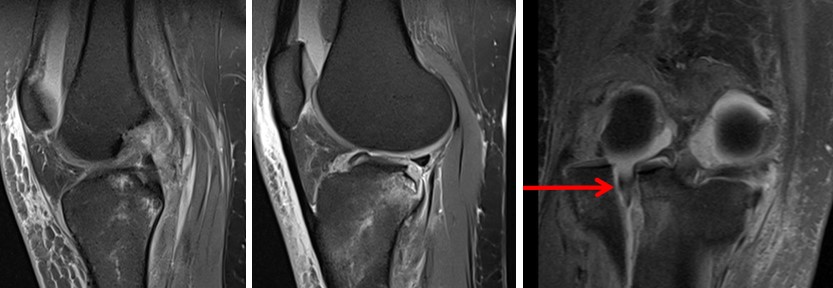

Магнітно-резонансна томографія (МРТ) показана для оцінки супутніх ушкоджень зв’язкового апарату, менісків, хрящової тканини та кісткового мозку:

- (Коллатеральні звязки, ПЗХ, ЗХЗ, меніски)

- Ушкодження латерального меніска:

- > 5 мм імпресія

- > 6 мм зміщення

Магнітно-резонансна томографія